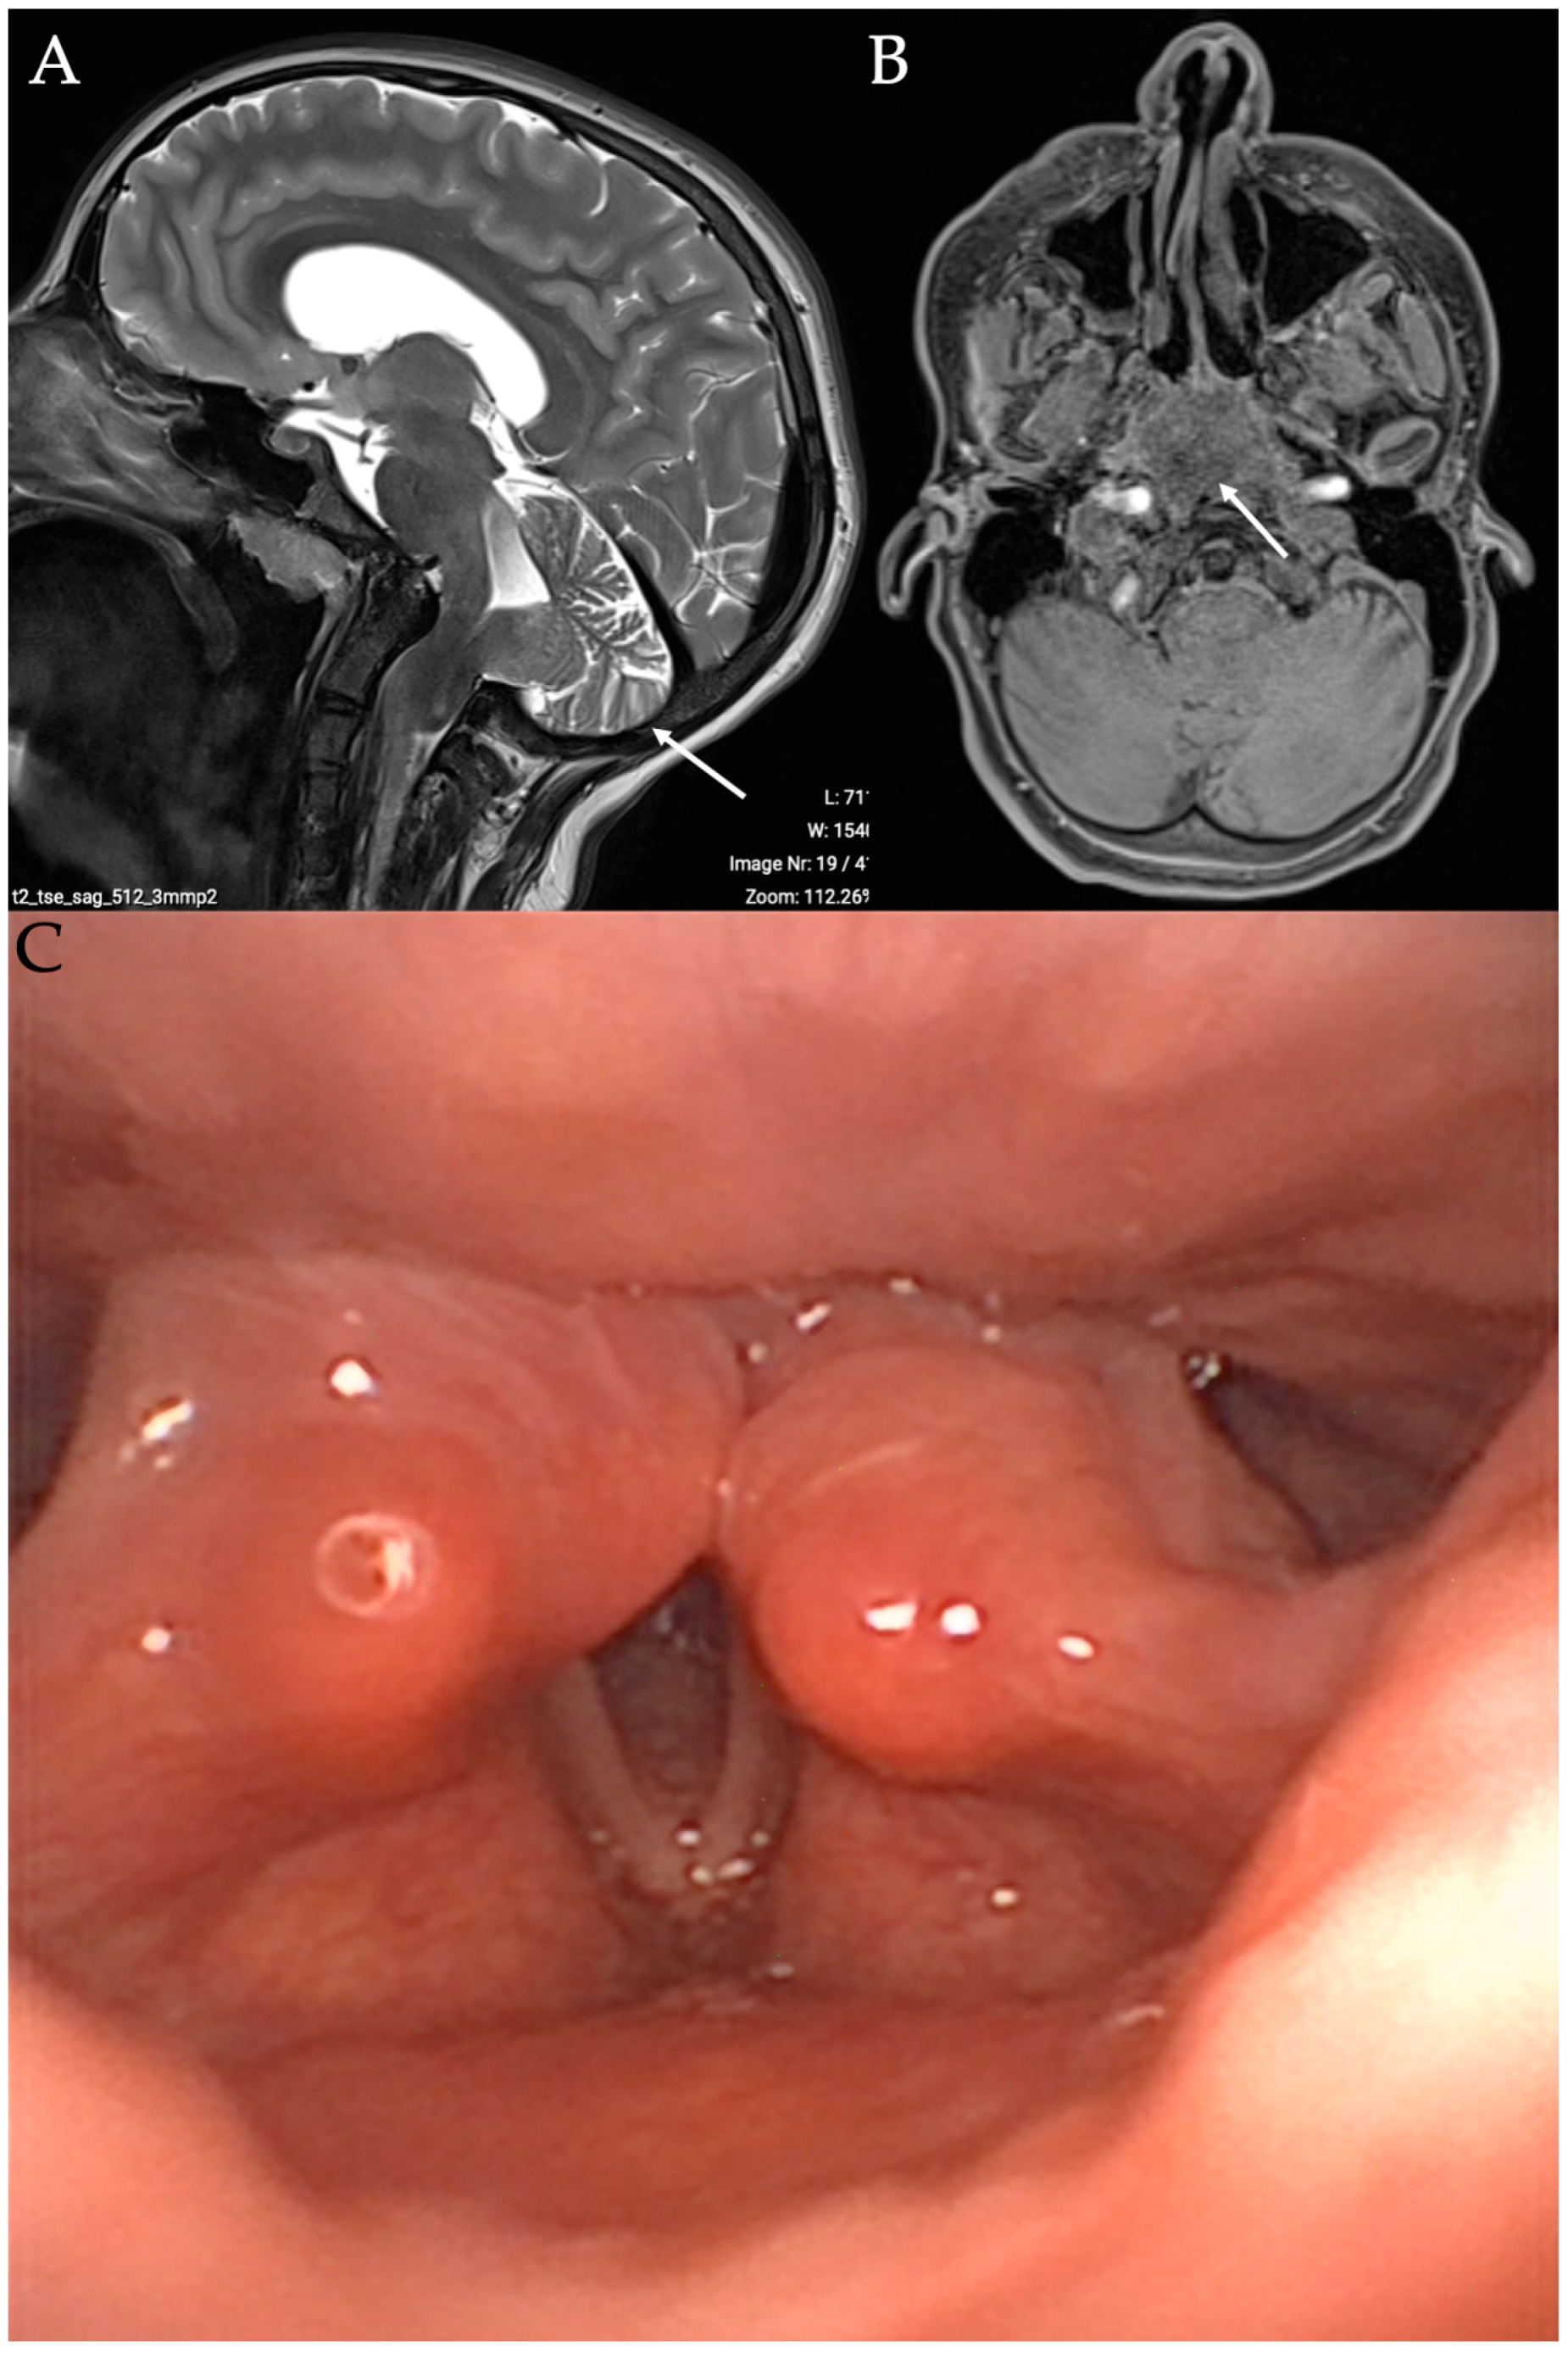

The PBVCP diagnosis is mainly clinical, with nasofibroscopy revealing partial or total immobility of the vocal folds. The neurological origin may be confirmed with laryngeal electromyography (LEMG) and additional examinations related to the etiology. Flexible fiberoptic endoscopy commonly reports paralyzed vocal folds in an adduction position due to abductor paralysis [1]. Primary symptoms of PBVCP include stridor, dyspnea, dysphagia, coughing, choking, apnea, or feeding difficulties. Dysphonia is not a primary symptom regarding the adduction position of the paralyzed vocal folds. However, in some cases, the vocal folds may be in an abduction position (Figure 1), which may lead to a different clinical presentation with aspiration, aphonia, and severe dysphagia. The rapid detection of PBVCP with abduction-positioned vocal folds is important due to the risk of severe pneumonia related to aspiration and penetration. In some cases, PBVCP with abduction-positioned vocal folds is related to bilateral vagus nerve paralysis, which is additionally associated with partial deinnervation of the constrictor muscles and severe dysphagia. Importantly, children with BVCP may be asymptomatic for several months, which delays the diagnosis and treatments when the child does not recover vocal fold motion [4,5]. A differential diagnosis with posterior glottic stenosis is important. During flexible fiberoptic endoscopy, the laryngeal posterior commissure and cricoarytenoid joints may appear more edematous in posterior glottic stenosis compared to PBVCP. However, it remains difficult to differentiate both conditions during the clinical examination. In direct suspension laryngoscopy, the cricoarytenoid joints are fixed in posterior glottic stenosis due to joint fibrosis. In PBVCP, the mobility of the arytenoid joints is relative or total during laryngeal palpation. Laryngologists need to document all comorbid conditions during suspension laryngoscopy, including subglottic stenosis or tracheomalacia. The differences between PBVCP and posterior glottic stenosis are difficult to objectify during suspension laryngoscopy, which, consequently, does not represent the gold standard approach for diagnosis.

Figure 1.

Image of bilateral vocal fold paralysis in abduction position. Image of child with bilateral vocal fold paralysis in abduction position and with Arnold–Chiari type II malformation. T1 MRI in sagittal (A) and axial (B) section reported herniation of hindbrain into low occipital or high cervical meningoencephalocele. Anatomical picture (C) describing anatomic relation between C1 and following cranial nerves: glossopharyngeal, vagus, and hypoglossal. Arrow is related to the Arnold-Chiari features at the imaging.